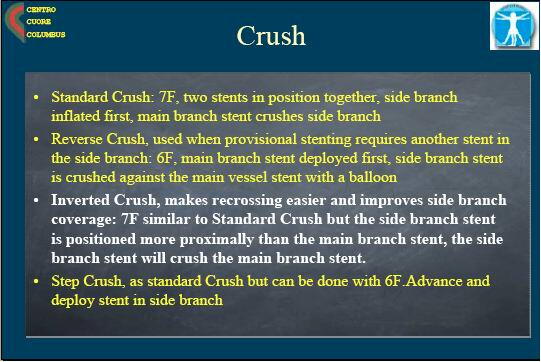

colombo���g�p���Ă���N���b�V���́Astandard crush, reverse crush(provisional

crush)

, step crush�i����́ATRI�ł̃N���b�V���ł���ˁB�j�ŁA�����搶�̂́Ainverted

crush�Ƃ��������ł��B